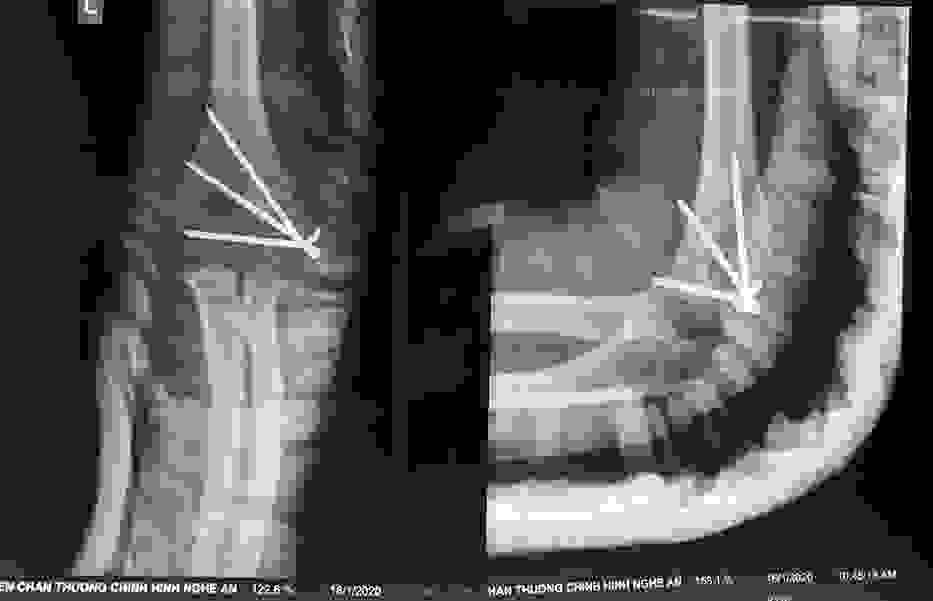

Phẫu thuật thành công ca bệnh hiếm gặp...khớp giả bẩm sinh xương chày

26/06/2019 17:00

Đã xem: 3474

Bệnh viện Chấn thương- Chỉnh hình Nghệ An, vừa phẫu thuật thành công cho bệnh nhi khớp giả bẩm sinh xương chày